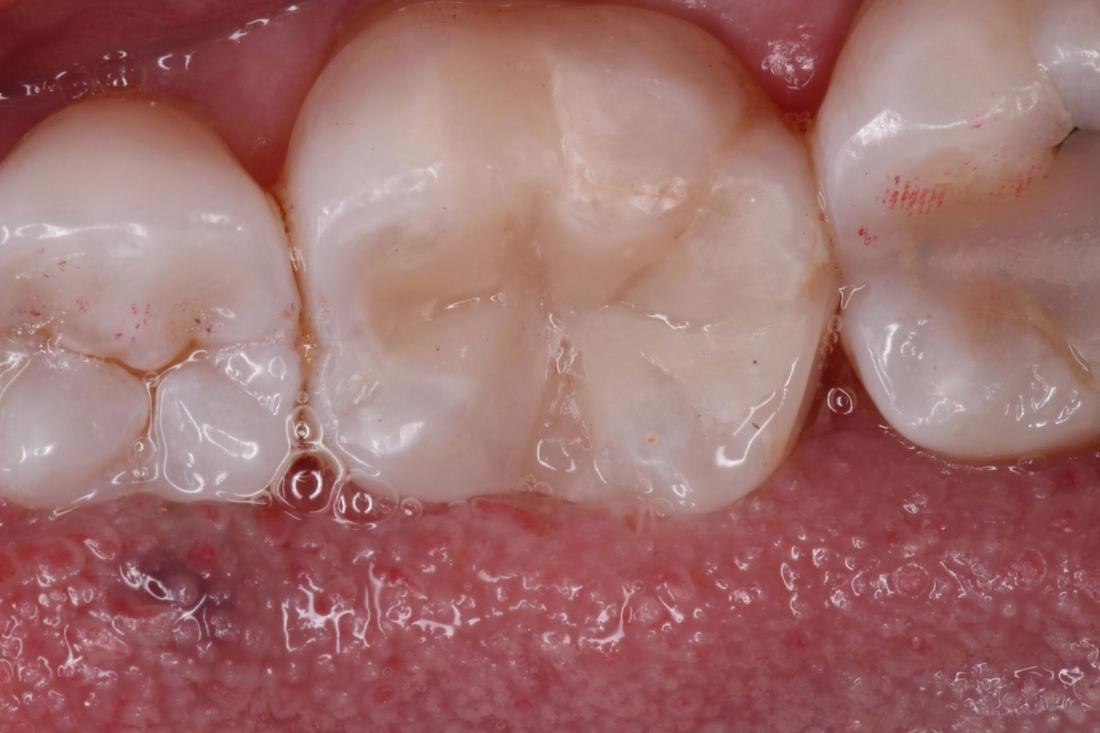

Our patient flew in from out of town to have this filling replaced. The edges of the filling were starting to leak, allowing bacteria to damage the tooth underneath the filling. A dental dam was used to isolate the teeth. We removed the old filling and replaced it with a new tooth colored filling.